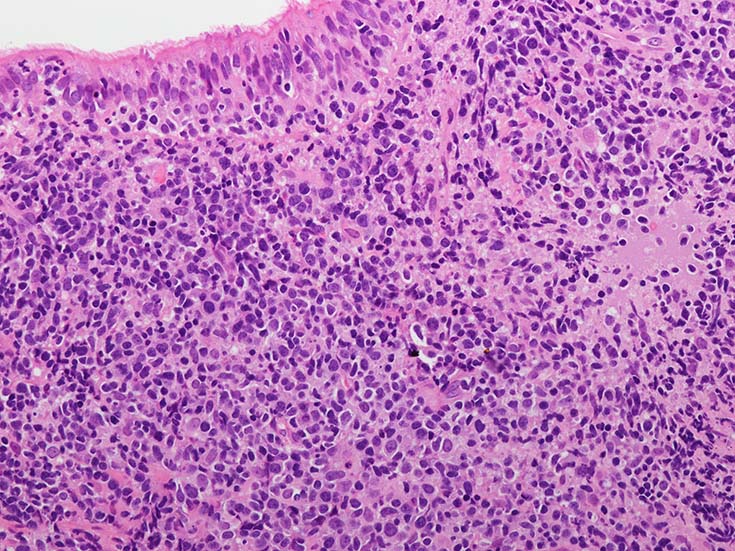

• 組織学的に,LyGは,様々な割合のリンパ球と大きなEBV+芽球からなる血管中心の浸潤を特徴としており,その中にはHRSに類似した特徴を示すものが出現する. 血管浸潤とそれに伴う多量の凝固壊死が典型的な所見である.

• Grade3; EBV+芽球の豊富な集合体(50個/HPF以上)と背景のT細胞が目立つことが特徴. グレード3の病変は,EBV+ DLBCLと同様のスペクトラムにはいる. (EBV+ DLBCLと診断したほうがよい[WHO5th classification]

血管周囲性に大型類円形核や不整形核をもつ腫瘍細胞がシート状密に浸潤増殖している. Mitosisが多く認められる.細血管閉塞や破壊の所見がある.

間質にもシート状の腫瘍細胞浸潤がある. 大小 pleomorphicな傾向.(A, B). necrosisが認められる(C). 細気管支上皮直下まで密な浸潤あり, 小型リンパ球が混在している.(D)

血管中心性浸潤. 障害された血管内に血栓が形成されている.CD20陽性細胞がシート状密に浸潤, CD3陽性T細胞が多く混在している. EBER-ISH陽性 EBV感染細胞が多数認められ, >50 hpf, 定義より Grade3となる. 陽性細胞のサイズは大小さまざまであることに注意. Lymphomatoid granulomatosisの病態(WHO5thの診断では EBV-positive diffuse large B-cell lymphomaになる)をとっているが MTX-associated LPDの一型とするべき症例かもしれません.